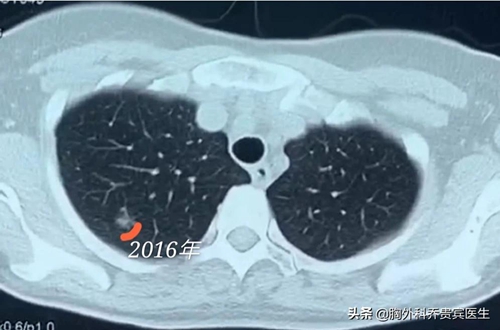

一位50多岁的女性,2016年10月做CT检查时发现右上肺有一个磨玻璃结节。今年复查时,发现结节已经明显变大。这是一种恶变的信号,应该及时手术处理。

第三个方面,就是判断结节的生长速度。也就是说对于非常小的结节,如果小于8毫米或者6毫米,就需要复查。前后对比这个病灶生长的快慢,如果生长慢说明它是良性的,如果生长快就能提示它是恶性的。因此,对于这些小的病灶,一般来说医生都是建议进行随访观察的。